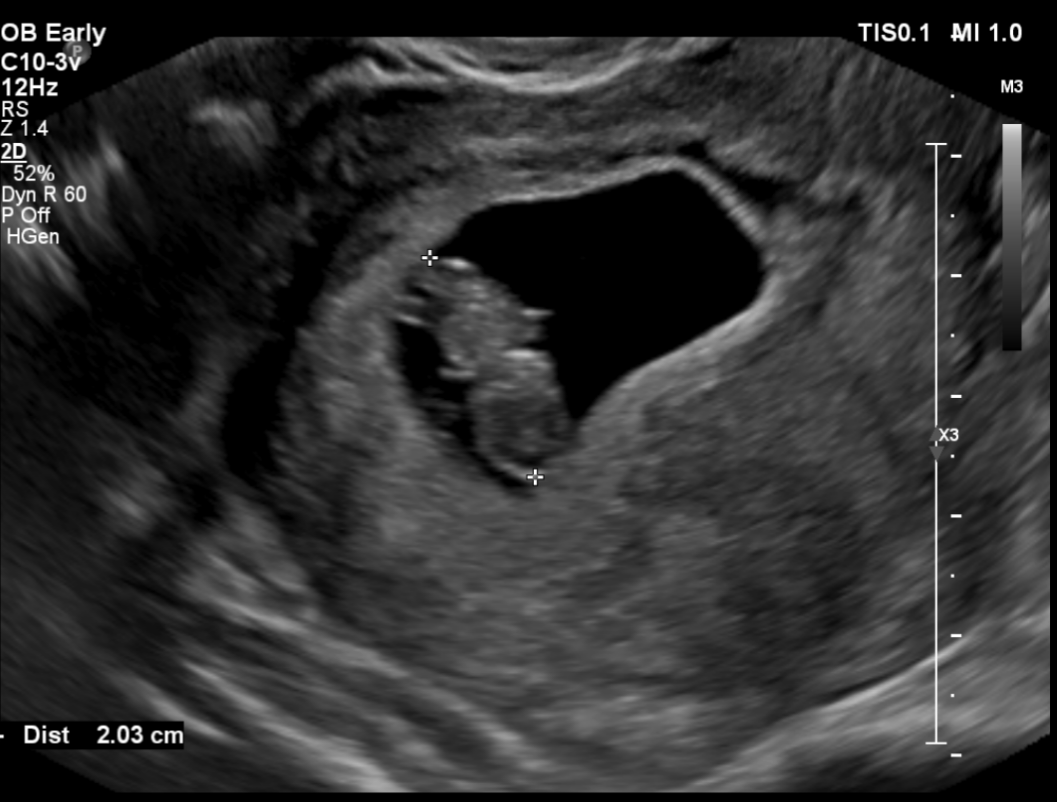

임신 8주 차 초음파 검사 ( 8주 5일 차 초음파 사진)

첫 트롱이 사진 짜잔~~ 젤리곰 이다 >. < 주수에 맞게 잘 자라고 있는 트롱이~ 심박수도 176 bpm으로 정상!

사실 초음파 검사 당시엔 아기 모습을 보지 못했어요~ 검사해주는 분께서 화면으로 보여주지도 않고 아무 말 없이 혼자 보면서 검사를 하시더라고요~ 그래서 저희 남편만 화면으로 확인하면서 너무 귀엽다고 잘 자라고 있다고 ㅠㅠ 저를 안심시켜줬습니다.

검사가 끝나고 전 메일로 받은 초음파 사진으로 처음 우리 아이를 봤어요~! 보고 나서 너무 귀엽고 제 뱃속에 이 작은 생명이 있다는 게 너무 신기해서 울었어요~ ㅜ.ㅜ~ ㅋㅋㅋ